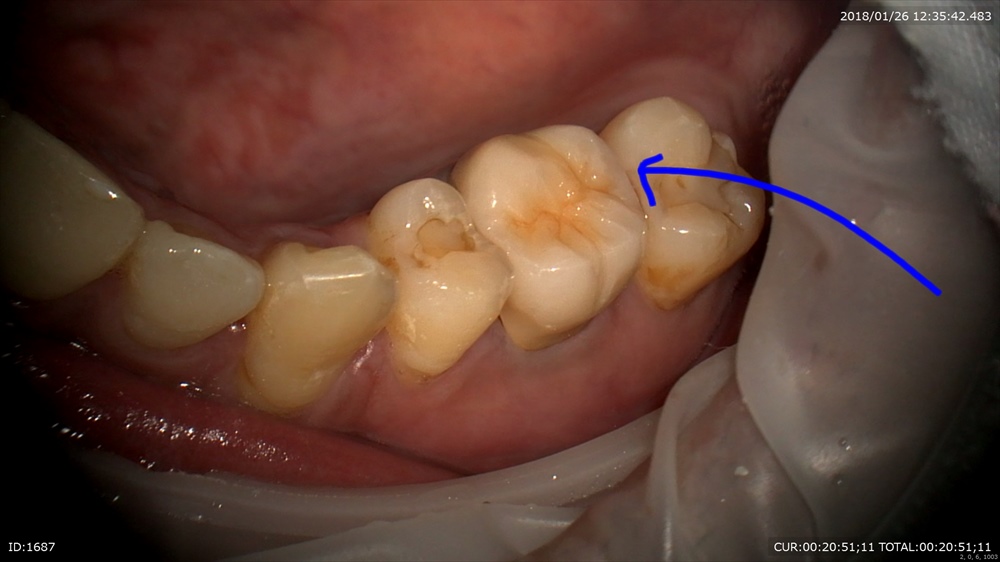

次のケースはかぶせ物のセット。仮歯を外して

綺麗に。歯肉OK。

綺麗にフィット。ハイブリット。

かみ合わせ大事